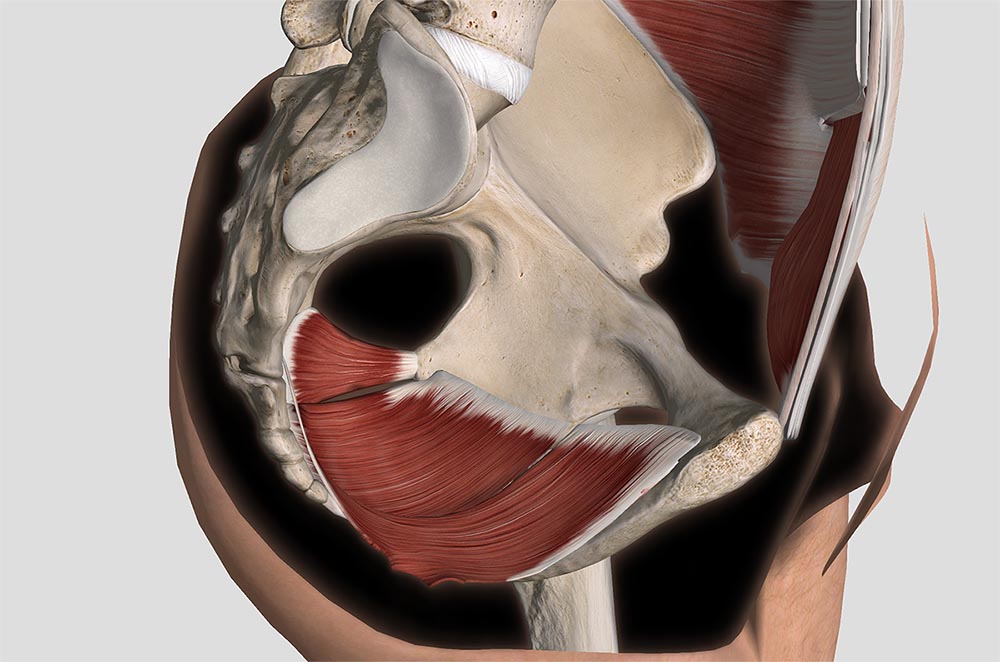

尿生殖隔膜は深会陰横筋、骨盤隔膜は肛門挙筋が主体をなす。(p.218 肛門挙筋, 尾骨筋, p.219 陰部の筋と神経の分布)

外閉鎖筋は閉鎖神経支配の内転筋群に分類されるが、股関節外旋の作用もあり、外寛骨筋に分類される場合もある。深層外旋六筋のひとつにもなっている。(p.272 大腿内面の筋 (内転筋群))

3 × 内閉鎖筋

内閉鎖筋は骨盤内で閉鎖膜内面から起こり、後方に走行し、小坐骨孔の縁で直角に曲がり転子窩に停止する。(p.266 外寛骨筋)

4 × 梨状筋

仙骨の前面より始まり、大坐骨孔を通過して大転子上端の後縁に停止する。(p.266 外寛骨筋)

会陰の中央、すなわち男性では肛門と尿道球、女性では肛門と膣前庭の後交連との間を、狭義の会陰という。この皮下には、肛門括約筋や会陰横筋とその筋膜が結合する会陰腱中心がある。会陰腱中心と坐骨結節を結ぶ線より前方を尿生殖隔膜部(尿生殖三角)、後方を骨盤隔膜部(肛門三角)と呼ぶ。骨盤腔の側壁の大部分は内閉鎖筋と梨状筋でおおわれるが、恥骨後面と内閉鎖筋の内面の筋膜から幕状に肛門挙筋が起こり、肛門および肛門と尾骨を結ぶ正中線上の靱帯に終わるために、肛門挙筋の下面と内閉鎖筋の間にV字状の陥没ができる。この陥没を坐骨直腸窩といい、大量の柔らかい脂肪組織で埋められる。(p.227 会陰)